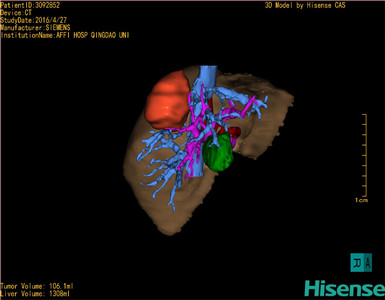

通过调节窗宽窗位调整CT序号,对肿瘤,肝实质,胆囊,下腔静脉,肿瘤,肝动脉、门静脉及肝静脉等进行三维重建;系统自动计算肿瘤体积和肝脏体积。

模拟手术操作,自动计算切除肿瘤体积。肝脏体积为1308ml,肿瘤体积为106.1ml,肿瘤体积为肝脏体积的8.1%,通过比对40-50岁正常肝脏体积为1368.38±279.24 ml,通过术前模拟手术,精准判断切除后剩余肝脏体积能耐受,避免肝衰竭发生。

术前三维重建:

重建图片